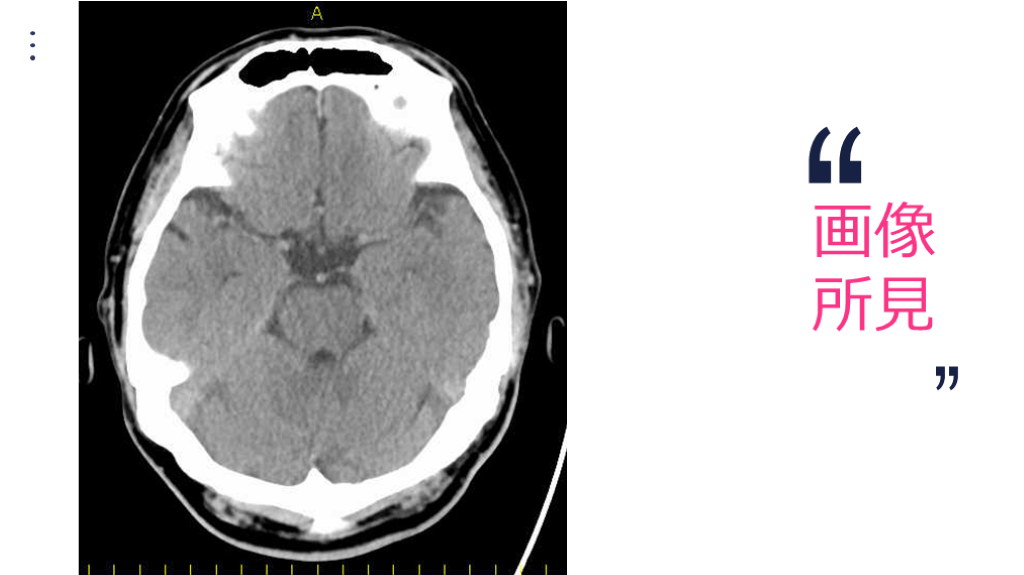

画像所見の重要性と解釈

画像 所見

画像 所見 FLAIR DWI